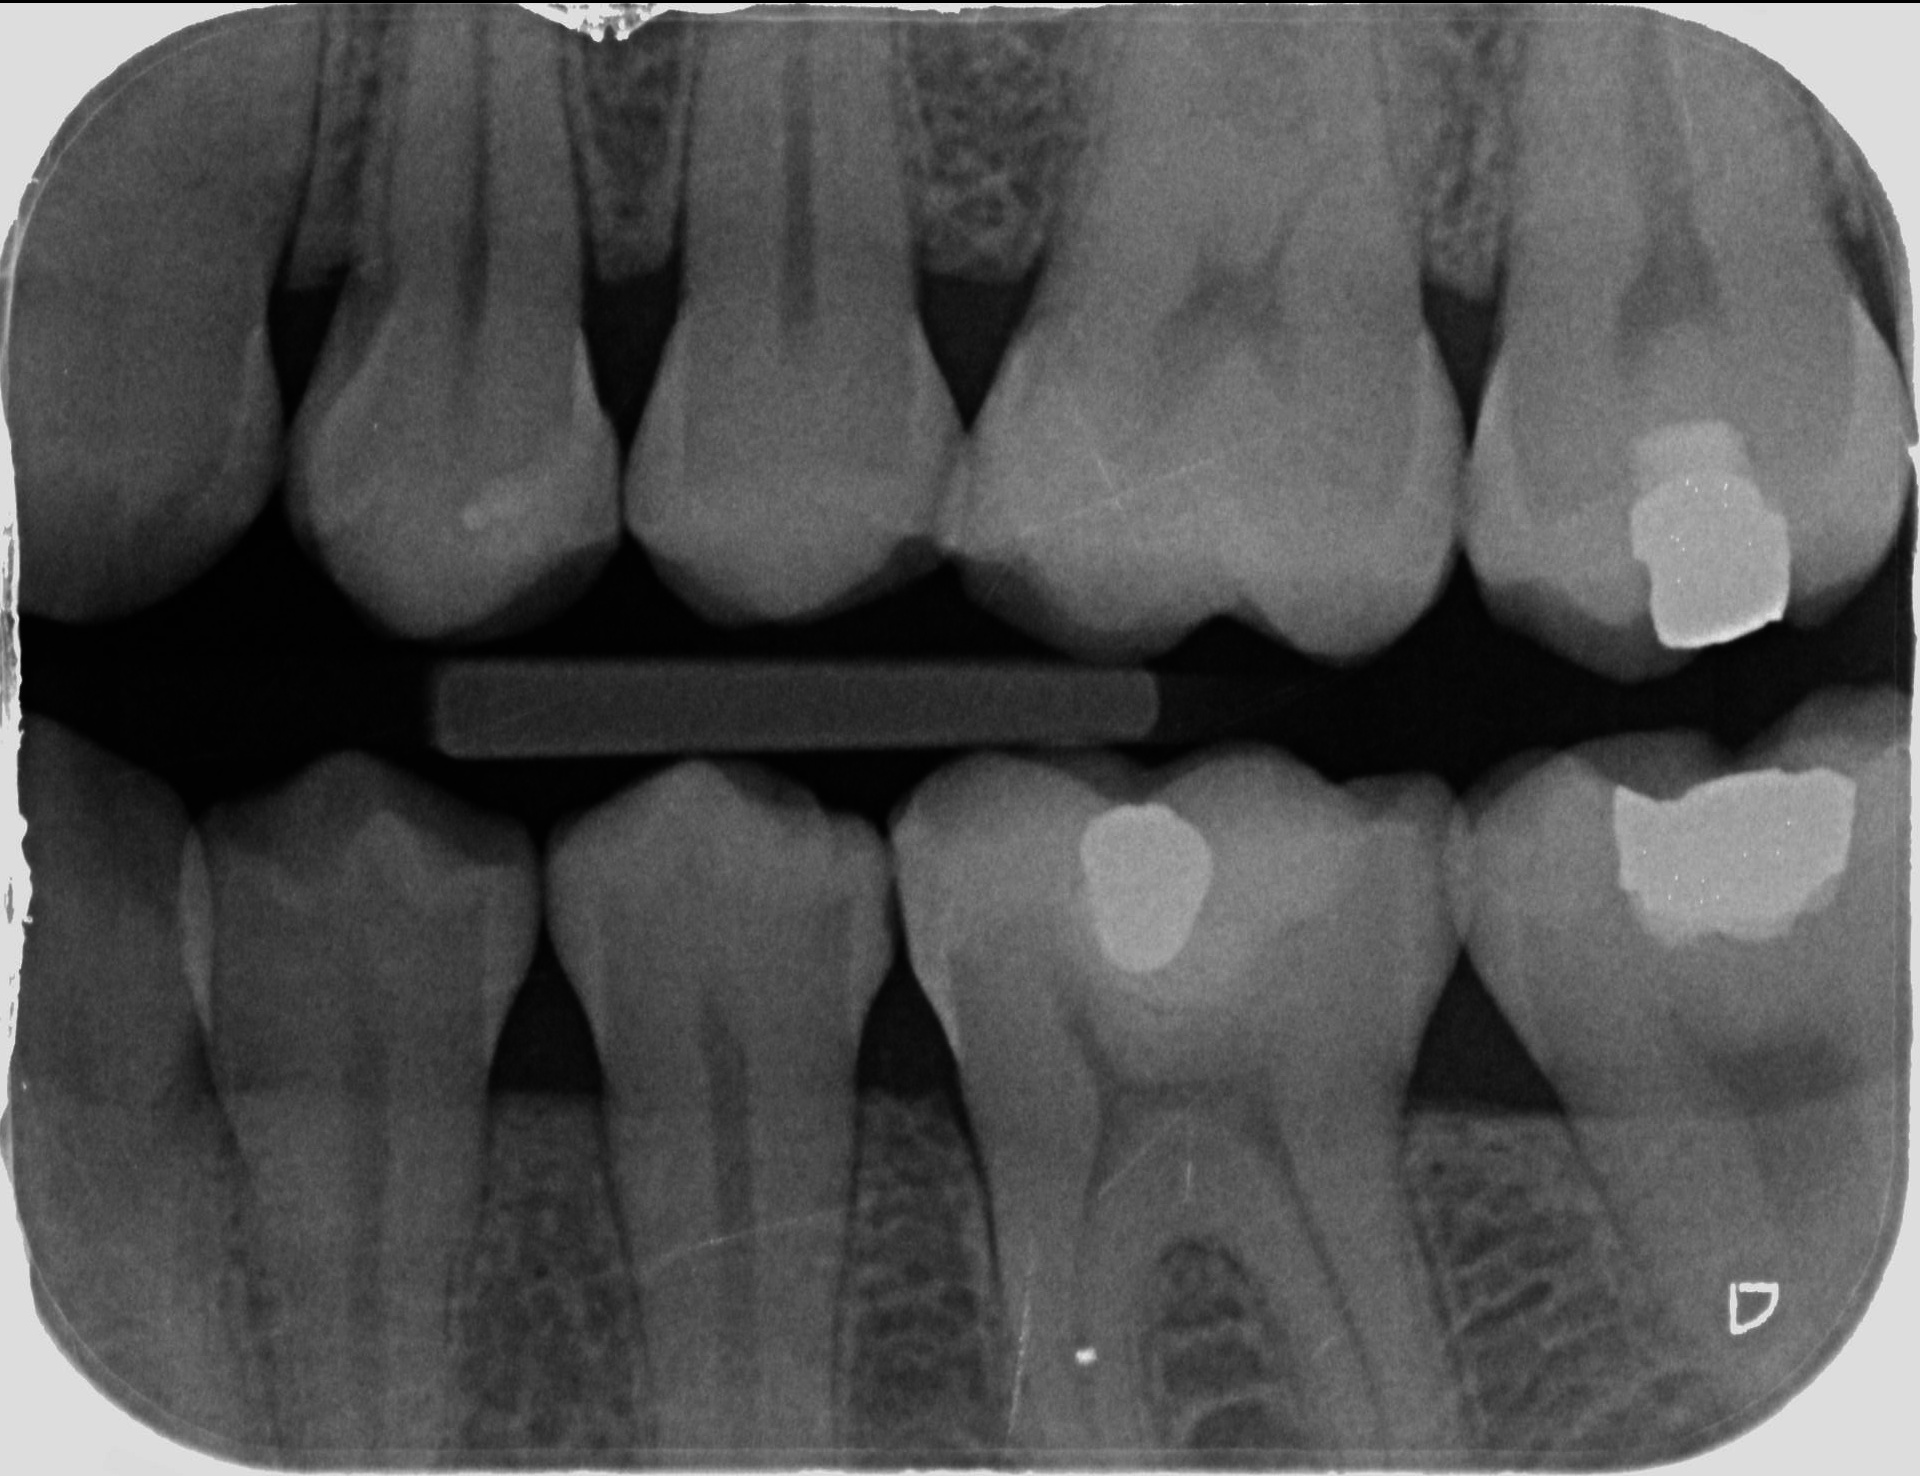

Preventivní rentgenový snímek